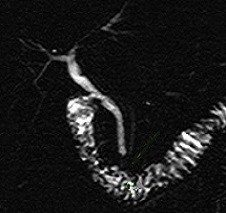

| |

|

Image radiologique CPRM d'une pancreas divisum

de type III. Le canal pancreatique principale est

s'aboucher pans la papille mineur duodenum . La voie

biliaire principale est s'aboucher au papille majeur

duodenum et.le canal pancreatique ventral est en

joindre avec une brache du canal dorsal . |